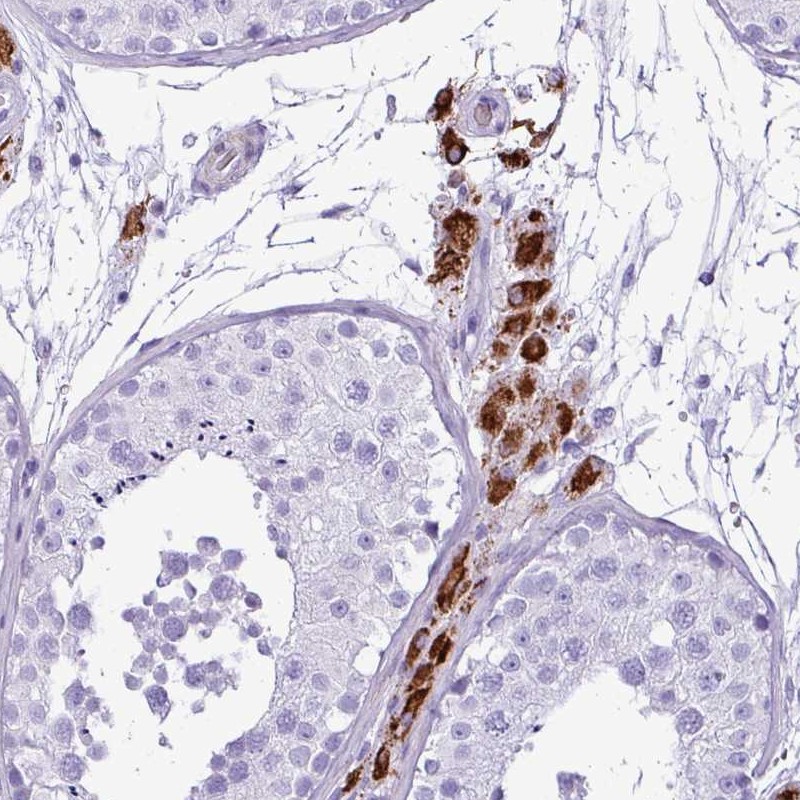

Immunohistochemical staining of human testis shows strong cytoplasmic positivity in Leydig cells.